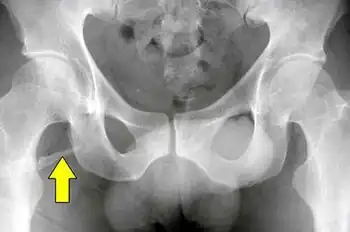

Pelvic digit

A pelvic digit, pelvic finger, or pelvic rib is a rare congenital abnormality in humans, in which bone tissue develops in the soft tissue near the pelvis, resembling a rib or finger and often divided into one or more segments with pseudo-articulations. Pelvic digits are typically benign and asymptomatic, and are usually discovered accidentally. Approximately 41 cases have been reported.[1]